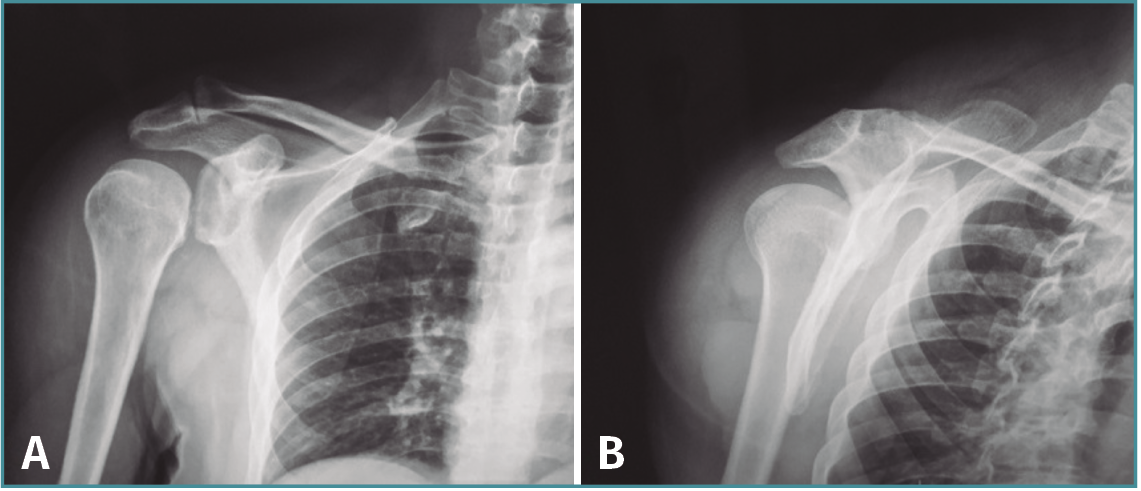

El postoperatorio transcurre sin incidencias, comprobándose la correcta congruencia articular en la resonancia magnética (RM) a las 4 semanas de la cirugía y en la artro-TC de control a los 2 meses de la misma (Figura 3). Tras la cirugía se mantiene inmovilización con cabestrillo durante 4 semanas, iniciándose el tratamiento físico rehabilitador mediante ejercicios pasivos y asistidos a la tercera semana, ejercicios activos a las 6 semanas y fortalecimiento muscular a los 3 meses.

Figura 3. Corte coronal de resonancia magnética (A) y corte axial de artrotomografía computarizada (B) postoperatorios en los que se observa la reducción de la cabeza humeral en la glena sin otras lesiones asociadas.